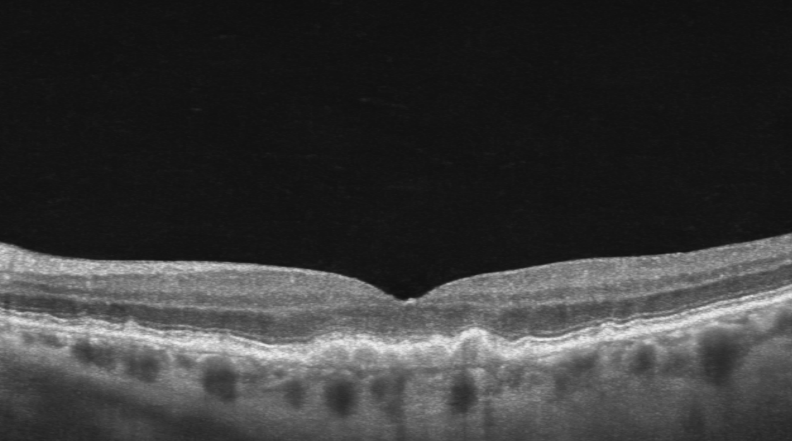

OCT image of drusen in Macular Degeneration

If macular degeneration progresses, the key concern is whether fluid develops in the retina.

The earliest signs are small pale deposits called drusen. These are like “cellular waste” that builds up in the retina over time.